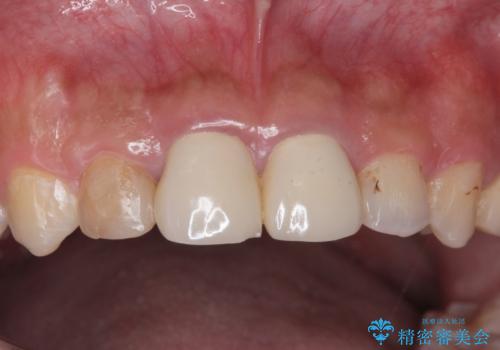

適合が良い被せ物が入りました。

隙間がなく被せ物が入ることによりう蝕の再発のリスクが低くなります。